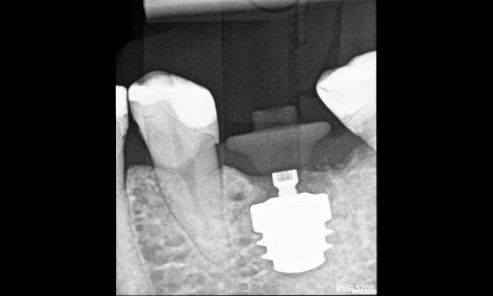

Radiographic and CBCT evaluation confirmed a vertical root fracture and failure of the previous endodontic treatment at tooth #36. Sufficient vertical and horizontal bone dimensions were observed, with D2 bone quality, indicating favorable conditions for immediate implant placement. The remaining teeth exhibited stable periodontal support and no significant bone loss (Fig. 2).

Fig. 2

Radiographic control confirmed proper implant and AHA positioning (Fig. 6).

Fig. 6